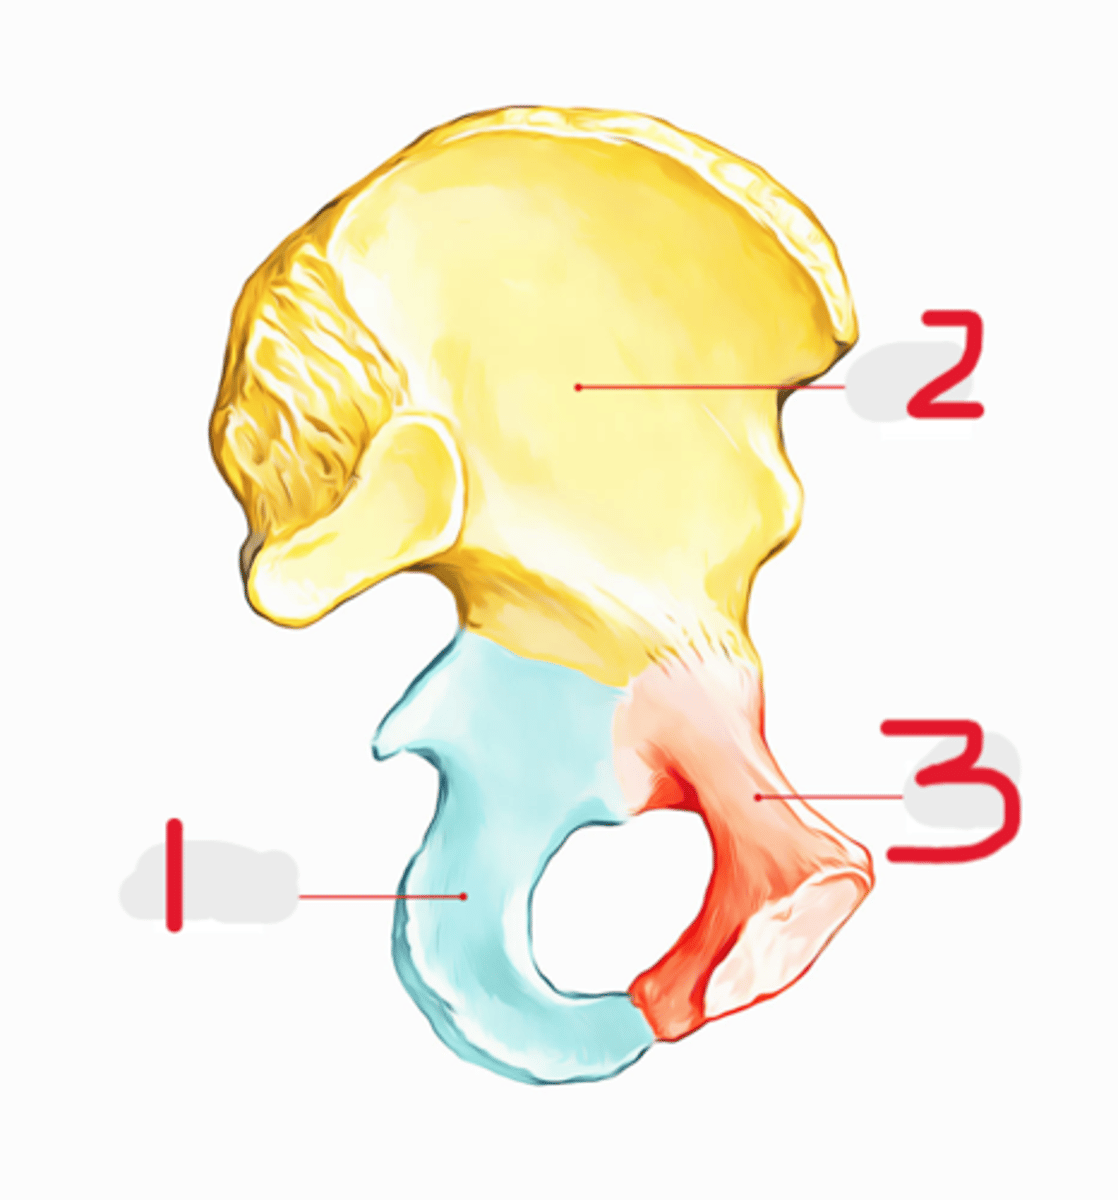

1) Ilium

2) Ischium

3) Pubis

What 3 bones make up the os coxae

Ilium

This is the largest and most superior portion of the bony pelvis

T or F: The ilium has a body

The ala

This is the large wing-like portion of the ilium

The ischium

This is the inferior portion of the os coxae

1) Body

2) Two rami

What composes the ischium (2)

Ischium

This forms the inferior portion of the acetabulum

The pubis

This forms the lower, anterior portion of the acetabulum

1) Body

2) Two rami

What is the pubis composed of (2)

Pubic bones

The bodies of the two _______ meet at the midline to form the pubic symphysis

The union of the pubic rami and the ischium

This forms the obturator foramen